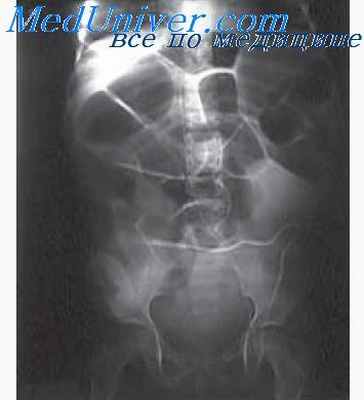

При рентгенологическом исследовании определяется скопление газовых пузырей и жидкого содержимого на большом протяжении кишки. Рельеф слизистой оболочки нередко приобретает крупнопятнистый или мелкокрапчатый рисунок. Складки при этом отечные, расширенные, местами сглаженные. Тонус повышен. Спазмированные петли чередуются с расширенными (симптом изолированности петель). Перистальтика чаще усилена, пассаж бария ускорен или, наоборот, замедлен. В толстой кишке определяется избыточное количество газа и жидкого содержимого. Энтерит необходимо дифференцировать от туберкулеза кишечника, регионарного энтерита, дивертикулита.